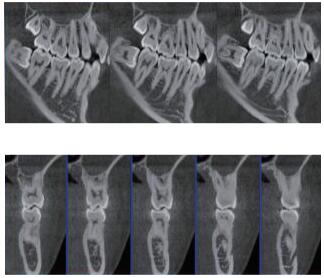

在口腔影像等細(xì)分領(lǐng)域,口腔CBCT的成像質(zhì)量優(yōu)于CT和普放。CBCT的X線利用率更高,且生成的圖像具備很高的各項(xiàng)同性空間分辨率??谇籆BCT能夠針對局部斷層曲面重建生成清晰無重疊的斷層影像以及3D影像,成像效果更好,有助于醫(yī)生的診斷,對于種植、綜合診斷、正畸等牙科診斷均有較大幫助??谇籆BCT技術(shù)優(yōu)勢如下:

三維重建任意斷層

專有三維重建算法,可提供任意位置高清斷層影像。

多平面組合重建

可同時(shí)觀察軸向面、冠狀面和矢狀面圖像,方便臨床診斷。